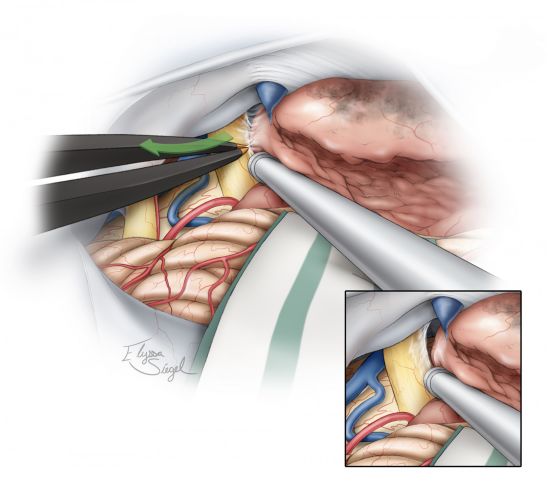

图9. 手术的下一步是将肿瘤壁从第V,VII,VIII颅神经和脑干上分离开(Dissection)。用显微镊子分离包绕神经的蛛网膜鞘从而将神经自肿瘤壁上游离(插图),这样做可以避免直接骚扰神经引起的医源性神经损伤。需保留蛛网膜及软脑膜界面。